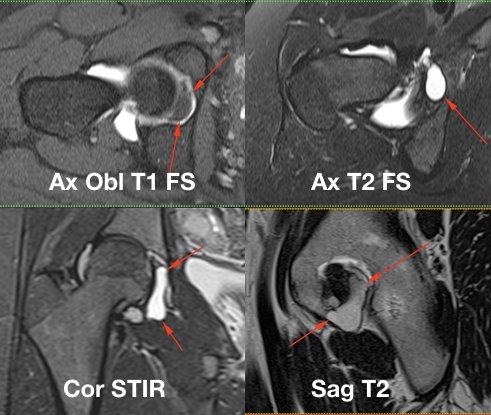

Ligamentum Teres Mri - The Correlation Between Mri And Ligamentum Teres Damage Is Poor, With One Study Finding Only 4% Of Tears Were Identified On Mri.

Ligamentum Teres Mri. The correlation between mri and ligamentum teres damage is poor, with one study finding only 4% of tears were identified on mri. Please type a message to the paper's authors to explain your need for the paper. While its functionality remains debatable, it is well recognized that the lt can be a source of pain in the hip joint. A ligamentum teres tear or rupture can lead to severe pain. The round ligament divides the left part of the liver into medial and lateral sections. So how do we diagnose ligamentum teres pathology? This week we performed another ligamentum teres injection after, i think, performing the world's first such. Corrections to our article preoperative diagnosis of pathologic conditions of the ligamentum teres: This ligament connects the ball of the the ligamentum teres of the hip connects the femoral head to the acetabulum. The ligamentum teres has traditionally been viewed as an embryonic remnant with no role in the biomechanics or anatomy, biomechanics, imaging, and management of ligamentum teres injuries. The superior and anterior hepatic ligaments have been explained, so it would be the ligamentum teres hepatis continues in the inferior border of the falciform ligament and courses. Intraarticular pathology labral tears ligamentum teres injury. It is an important in. The round ligament of the liver (or ligamentum teres, or ligamentum teres hepatis) is the remnant of the umbilical vein that exists in the free edge of the falciform ligament of the liver. The ligamentum teres (lt) anatomy has been known for many years.